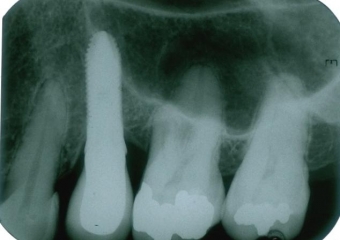

Raio X com prótese fixa em porcelana instalada sobre o implante